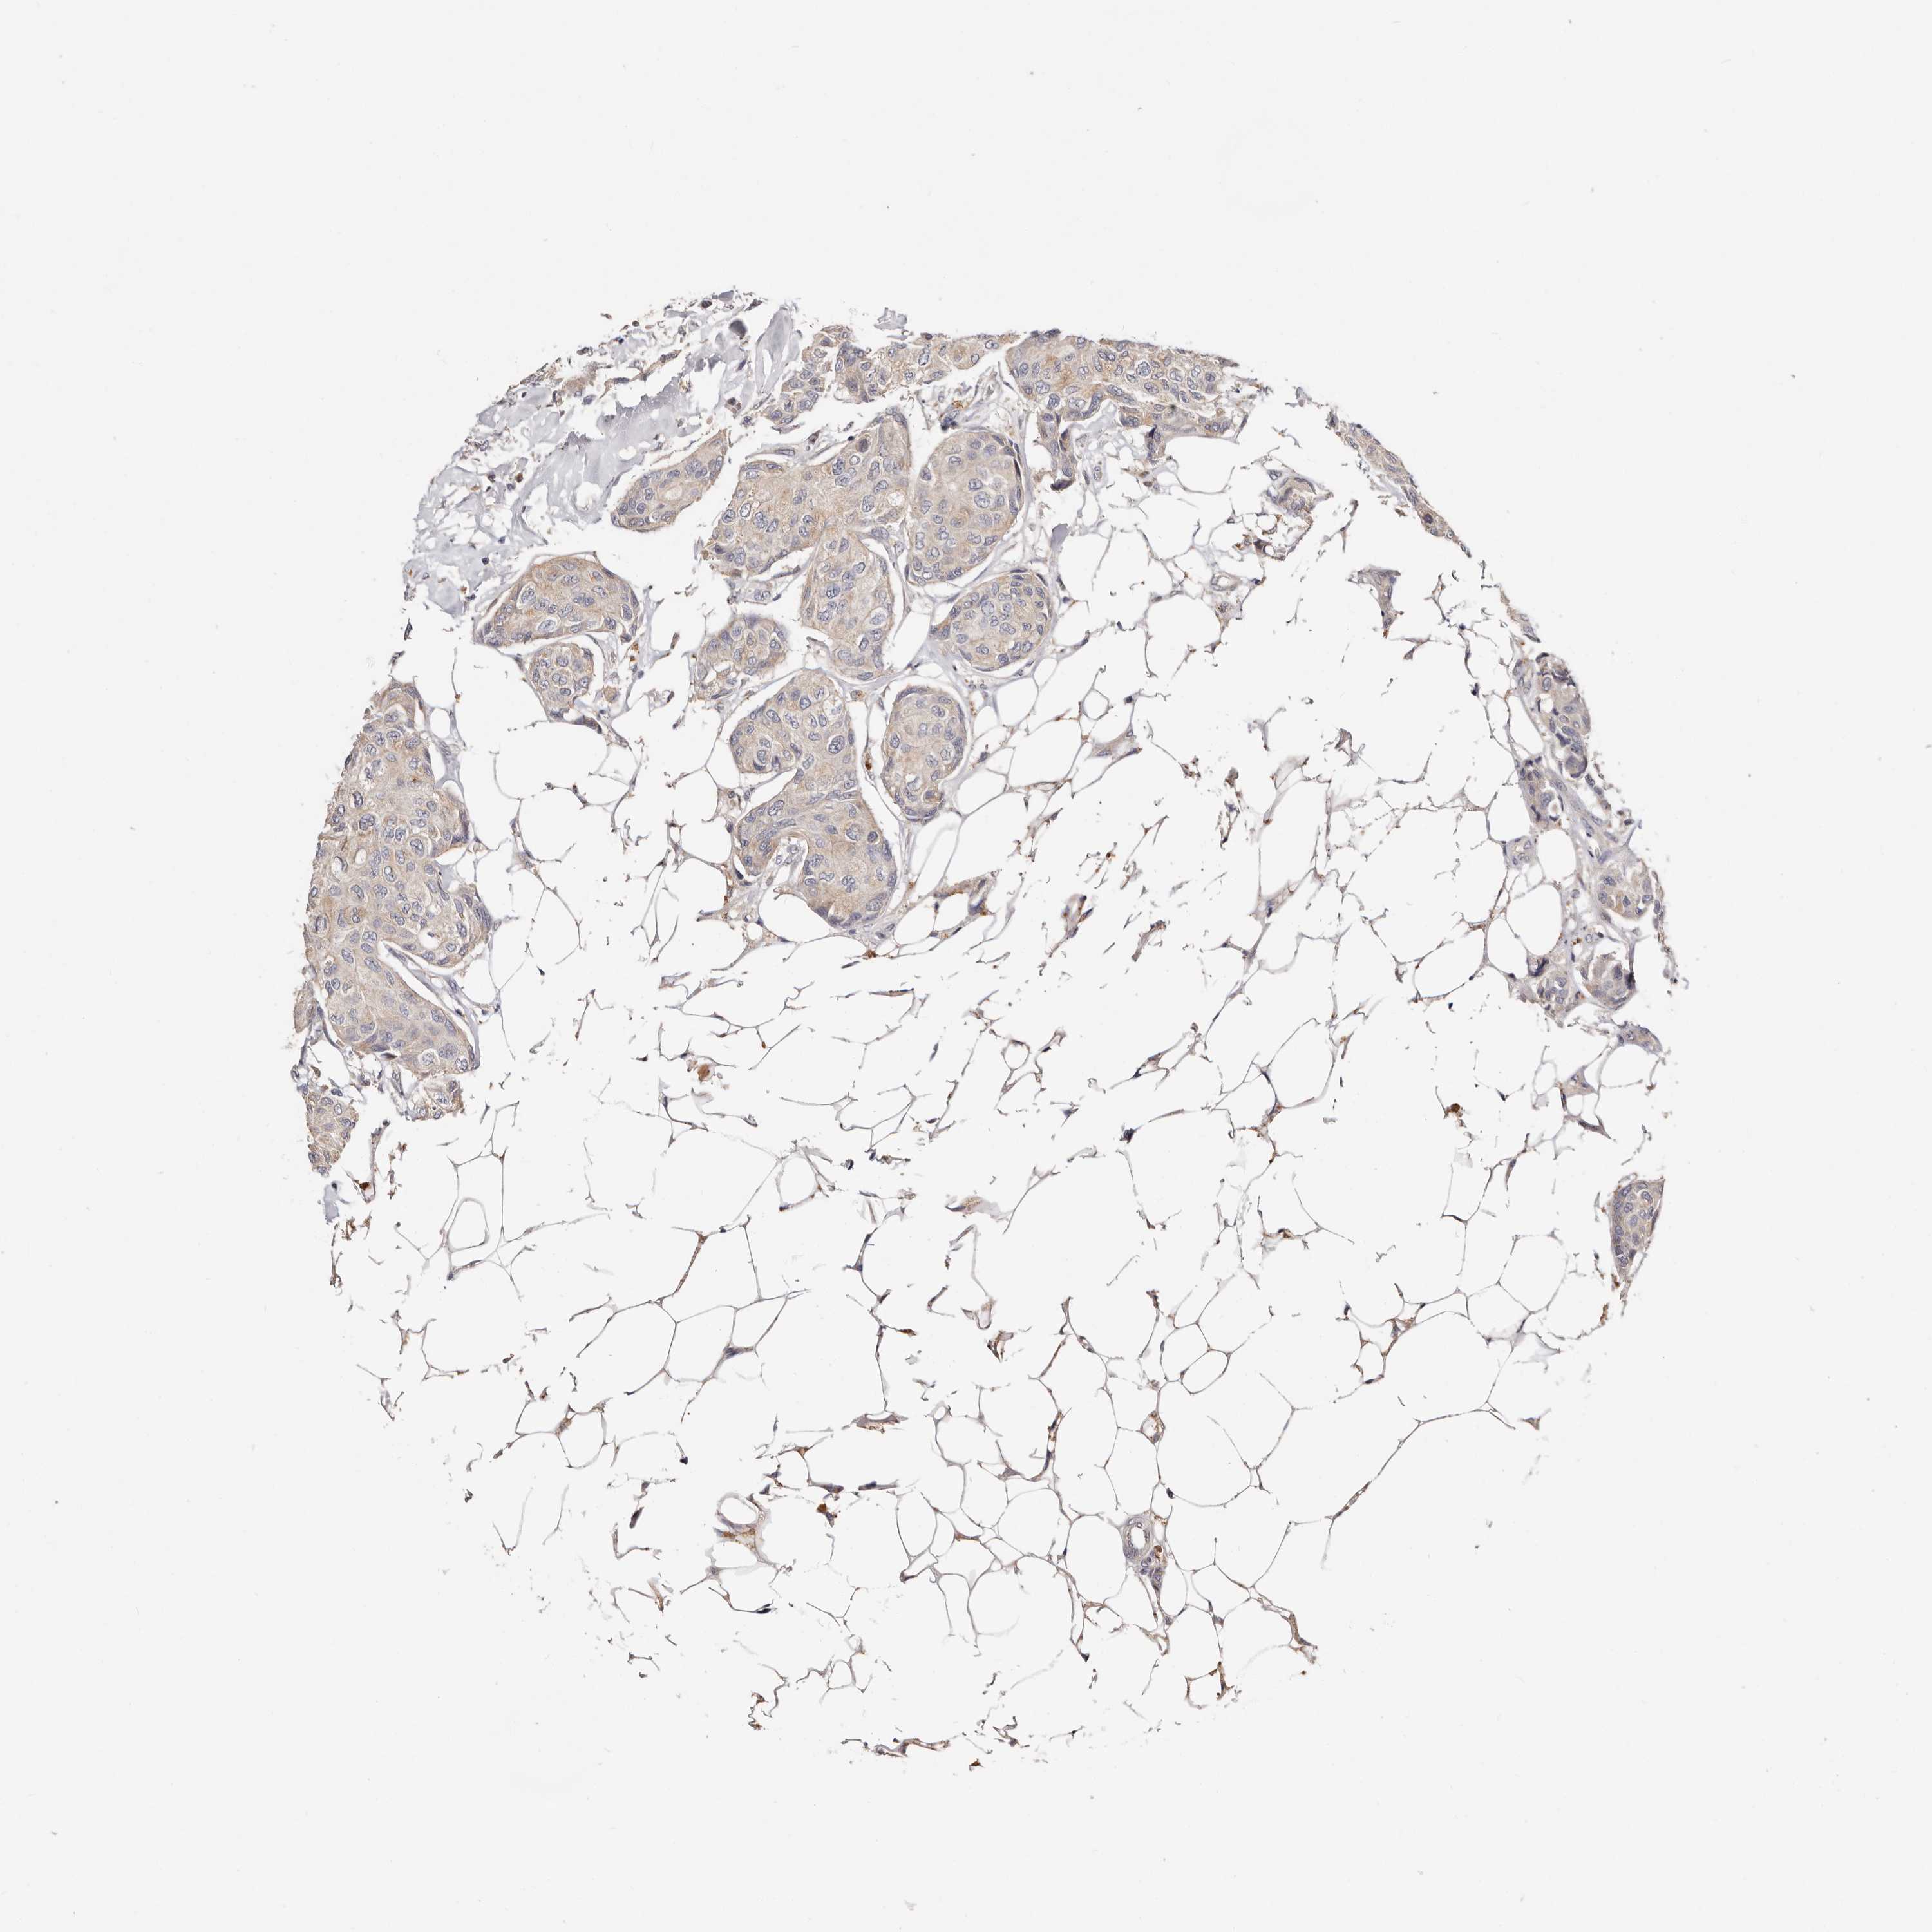

CANCER BREAST CANCER Show tissue menu

BRCA TCGA BRCA VALIDATION PROTEIN EXPRESSION